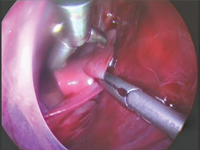

SurgeryA 2-month-old male infant was admitted to the Department of Pediatric Surgery with a suspected right-sided diaphragmatic hernia. After imaging studies were performed, it was decided to perform thoracoscopy. Intraoperatively, hypoplastic right lung tissue with a residual pleural cavity was found. The analysis of the present case and the diagnostic and therapeutic process carried out is an example that the imaging studies performed do not always allow us to make a correct preoperative diagnosis. Despite performing the examinations recommended in similar cases, making the correct diagnosis turned out to be possible only intraoperatively.